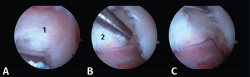

Figura 4. A: imagen artroscópica que muestra el ligamento peroneo-astragalino posterior (LPAP) (1); B: resección del LPAP con un sinoviotomo orientado medialmente contra la cara lateral del proceso posterolateral del astrágalo (PPA) (2); C: cara lateral del PPA después de la resección del LPAP.

El artroscopio se orienta ahora mirando inferiormente en dirección al primer espacio intermetatarsiano. La ventana del terminal de sinovectomía se apoya contra el calcáneo hasta visualizar la articulación subastragalina posterior, lateral al PPA.

Figura 5. A: resección de tejidos blandos en la parte superior del proceso posterolateral del astrágalo (1); B y C: realización de la artrotomía tibioastragalina posterior siguiendo una dirección horizontal.

- Primer paso: retirar el LPAP, completamente en caso de PPAH y parcialmente en caso de OT. La resección del tejido ligamentoso se realiza apoyando la ventana del sinoviotomo contra el lateral del PPA (Figuras 4 A, B y C).

- Segundo paso: eliminar el tejido blando en la parte superior del PPA. La ventana del sinoviotomo se gira 90° para apoyarse sobre la parte superior del PPA. Con ello, se realiza la artrotomía tibioastragalina y se escinde la cápsula hipertrófica de la articulación posterior. Es importante realizar movimientos en plano horizontal para preservar la continuidad del ligamento intermaleolar y evitar una artrotomía de trazo vertical que podría seccionar inadvertidamente dicho ligamento (Figuras 5 A, B y C).